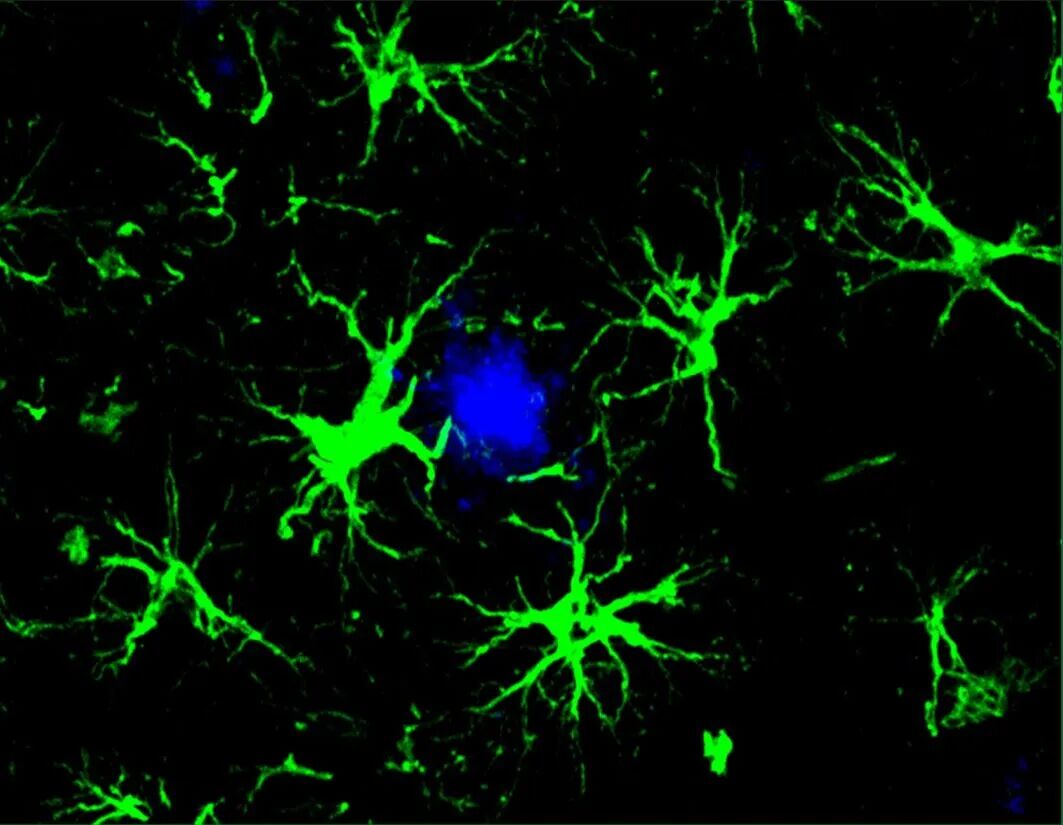

CAR-A疗法(绿色)成功地降低了小鼠大脑中有害的β-淀粉样蛋白斑块(蓝色部分)的数量(来源:Yun Chen,WashU Medicine)

小胶质细胞是存在于大脑中的免疫细胞,它们负责清除大脑中的“废物”,但在神经退行性疾病的情况下,如果受到过度刺激,这些细胞可能会出现功能障碍。为了减轻小胶质细胞的清洁负担,研究人员将大脑中数量最多的细胞类型——星形胶质细胞,改造成了能够清除淀粉样蛋白的“机器”——通过腺相关病毒(AAV)对星形胶质细胞进行基因改造,使其能够表达抗 Aβ 抗体的单链可变区(scFv),并将其与吞噬受体的细胞内结构域相融合(通过AAV-PHP.eB-GFAP体内递送CAR到中枢神经系统中的星形胶质细胞中)。

在这项新研究中,科学家们开发的CAR-A疗法只需注射一次就能防止小鼠体内淀粉样斑块的形成(在斑块开始形成之前接受治疗)。此外,对已经出现斑块的小鼠进行一次治疗,就能使淀粉样蛋白斑块的数量减少了一半。